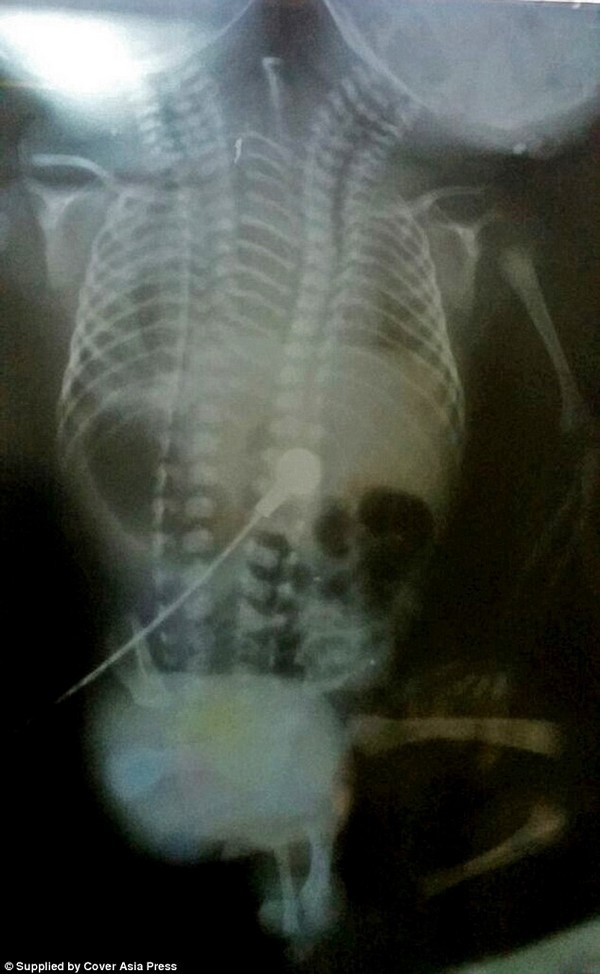

Mặc dù bề ngoài đứa trẻ có 2 đầu và một phần thân nhưng phim chụp X-quang cho thấy phần xương và các cơ quan nội tạng bên trong được tách rời. Các bác sĩ đã cân nhắc đến khả năng thực hiện phẫu thuật để tách rời 2 đứa trẻ nhưng ca dính liền quá phức tạp nên khả năng này là rất khó.

“Các ca phẫu thuật có thể được thực hiện trong một số ca sinh đôi dính liền, nhưng trường hợp này quá phức tạp và gần như không thể phẫu thuật”, bác sĩ Jai cho biết. “Mặc dù cặp sinh đôi có đầy đủ cơ quan nội tạng tách rời nhưng chúng đều dính liền bên trong một cơ thể, với chỉ 2 chân và 2 tay”.

| Ảnh chụp X-quang cho thấy 2 em bé có nội tạng tách biệt nhưng chứa chung trong một cơ thể |